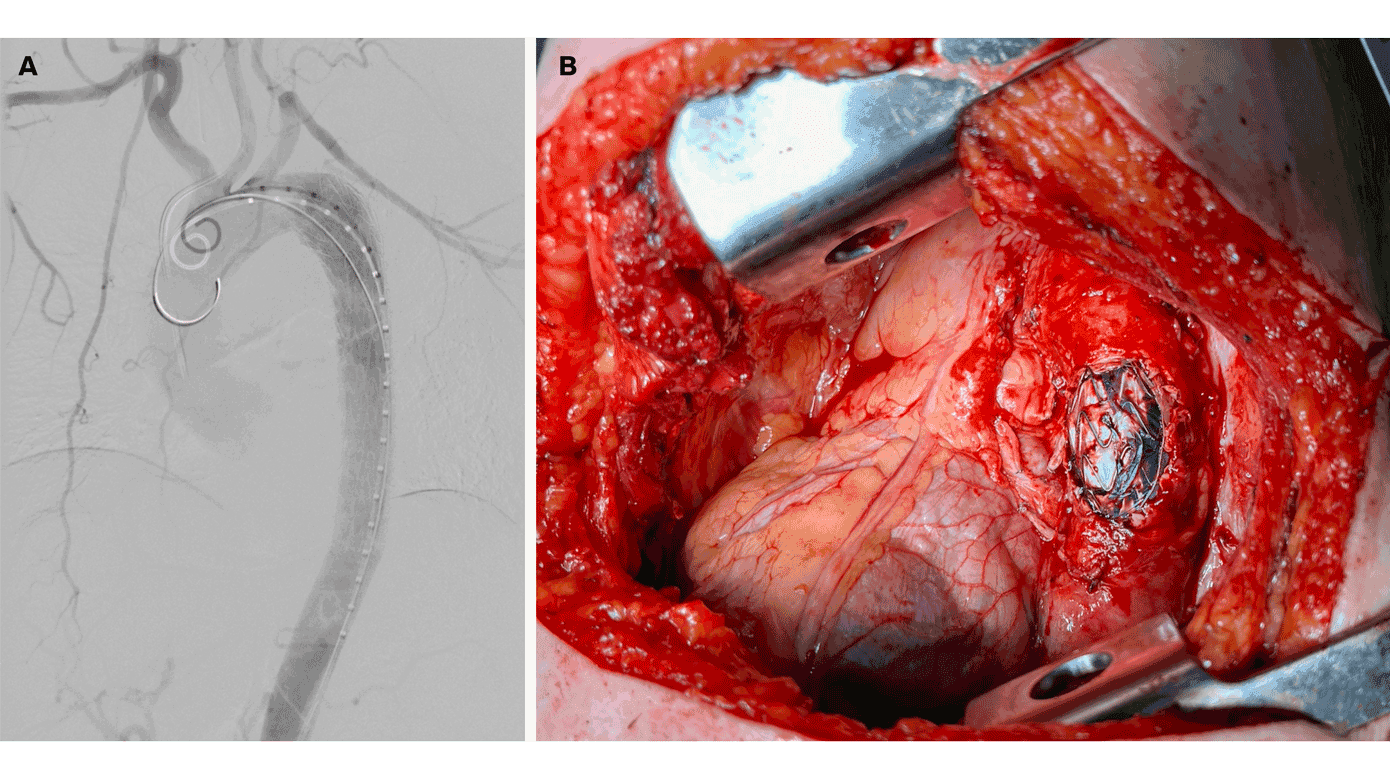

En 59-årig, aldrigrygende kvinde fik efter fem uger med hoste og træthed påvist en 45-mm PET-positiv tumor centralt i venstre underlap med indvækst i venstre overlap, mediastinum og aorta descendens. Biopsi viste pulmonalt adenokarcinom. Normalt er indvækst i centrale, vitale strukturer kontraindikation for lungekræftoperation, men ved multidisciplinært samarbejde i aortacentret imellem interventionsradiologer, kar- og thoraxkirurger blev det besluttet at tilbyde patienten en kurativt intenderet operation trods indvækst i aorta descendens. Operationen blev opdelt i to faser: Først blev der udført en endovaskulær stentbehandling af aorta gennem lysken (en såkaldt thoracic endovascular aortic repair: TEVAR) (A), og få dage efter blev der foretaget pneumonektomi, hvor stenten blev blotlagt, fordi aortavæggen blev reseceret (B). Det postoperative forløb var ukompliceret, og patienten modtog efterfølgende adjuverende onkologisk behandling.